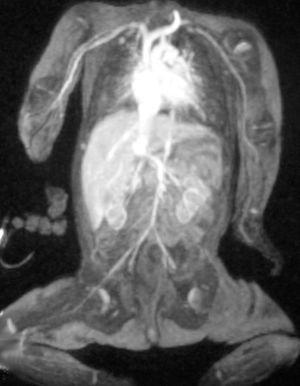

En la exploración física al nacimiento, se objetivó fenotipo sugerente de síndrome de Down. El análisis citogenético demostró trisomía 21. El ecocardiograma reveló una comunicación interventricular muscular pequeña y una comunicación interauricular moderada. La ecografía cerebral fue normal. Se realizó una ecografía abdominal donde se visualizó un hígado de tamaño y ecogenicidad normal con una vena porta de 0,17 cm unida a una vena suprahepática de 0,7 cm de diámetro que desembocaba en la vena cava inferior. La anastomosis entre la vena porta y la vena cava inferior se confirmó en la angiorresonancia magnética nuclear (figs. 1 y 2).

Figura 1.Angio-RM: anastomosis entre la vena porta y la vena cava inferior a nivel del hilio hepático.

Figura 2.Angio-RM: vena cava inferior retrohepática marcadamente dilatada hasta su entrada en la aurícula derecha. Leve disminución de calibre de la aorta abdominal.